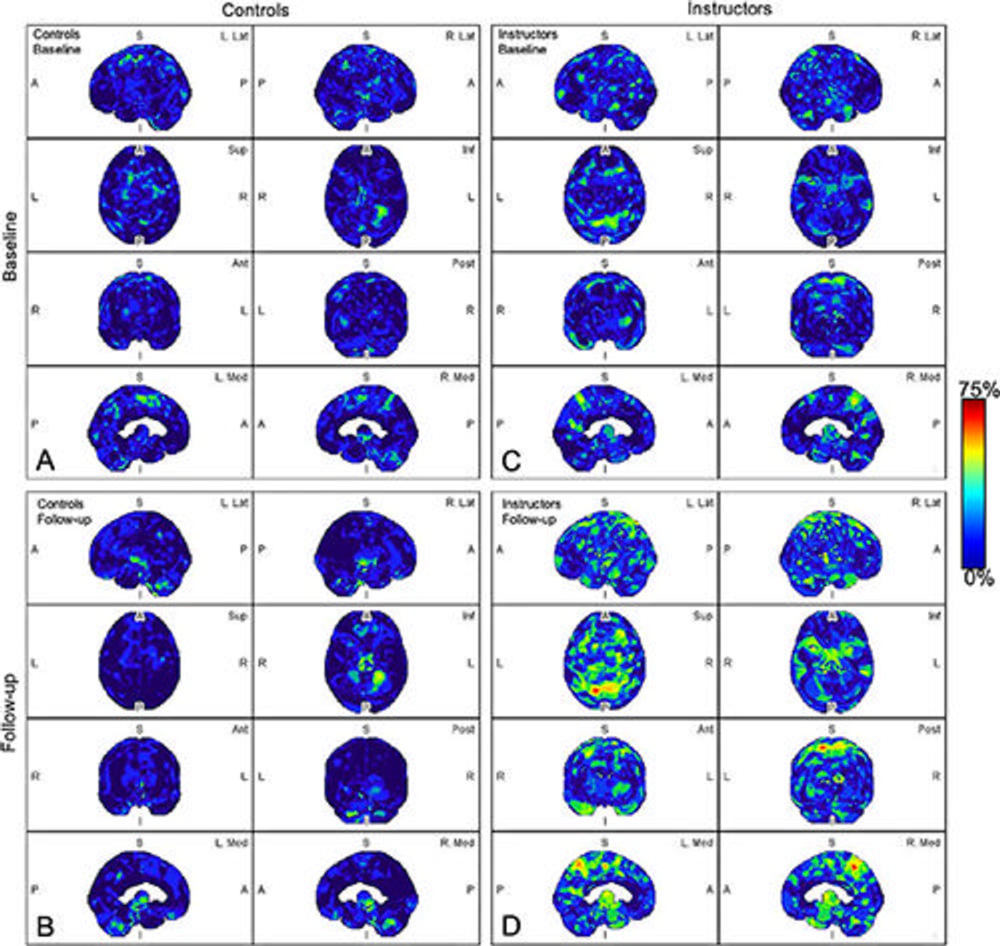

Figure 1. Parametric maps of amyloid deposition in healthy control participants (A and B) and blast-exposed military instructors (C and D) at baseline (A and C) and follow-up (B and D). The blue-to-red scale indicates the frequency of statistically abnormal amyloid uptake in a particular brain voxel. Whereas no abnormal amyloid uptake was identified at baseline or follow-up in healthy control participants (A, B) , amyloid deposition occurred most frequently in blast-exposed participants in the superior parietal lobules, precuneus, cingulum, paracentral lobules, and anterior temporal and occipital lobes (D) . A = anterior, Ant = anterior, I = inferior, Inf = inferior, L = left, Lat = lateral, Med = medial, P = posterior, Post = posterior, R = right, S = superior, Sup = superior.